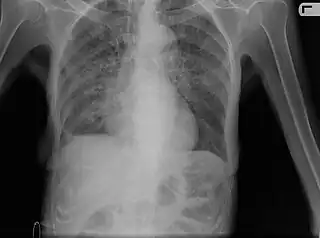

X-ray, showing bilateral interstitial infiltrates -

Miliary tuberculosis is a form of tuberculosis that is characterized by a wide dissemination into the human body and by the tiny size of the lesions (1–5 mm). Its name comes from a distinctive pattern seen on a chest radiograph of many tiny spots distributed throughout the lung fields with the appearance similar to millet seeds—thus the term "miliary" tuberculosis. Miliary TB may infect any number of organs, including the lungs, liver, and spleen.[5] Miliary tuberculosis is present in about 2 percent of all reported cases of tuberculosis and accounts for up to 20 percent of all extra-pulmonary tuberculosis cases.[6]

Testing for miliary tuberculosis is conducted in a similar manner as for other forms of tuberculosis, although a number of tests must be conducted on a patient to confirm diagnosis.[7] Tests include chest x-ray, sputum culture, bronchoscopy, biopsy, CT/MRI, blood cultures, fundoscopy, and electrocardiography.[1] The tuberculosis (TB) blood test, also called an Interferon Gamma Release Assay or IGRA, is a way to diagnose latent TB.A variety of neurological complications have been noted in miliary tuberculosis patients—tuberculous meningitis and cerebral tuberculomas being the most frequent. However, a majority of patients improve following antituberculous treatment. Rarely lymphangitic spread of lung cancer could mimic miliary pattern of tuberculosis on regular chest X-ray. [14][4]